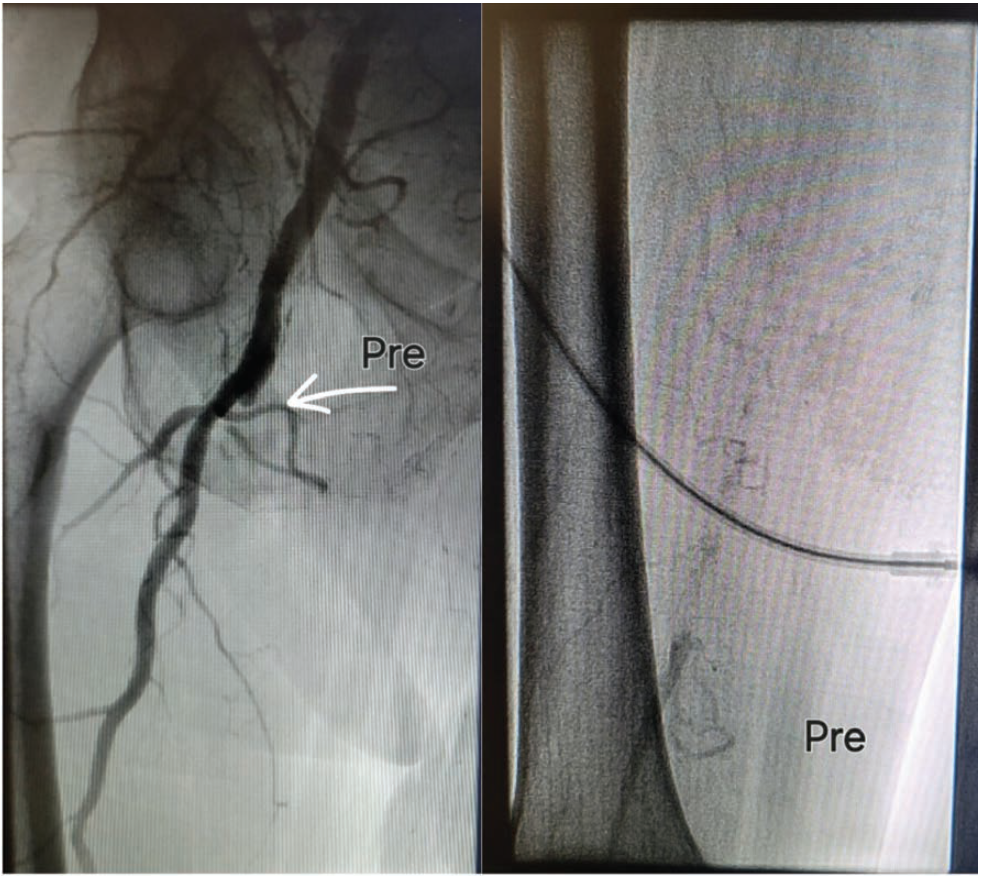

A recent arterial duplex ultrasound of the lower extremities was abnormal, demonstrating monophasic waveforms indicative of a total occlusion of the right superficial femoral artery (SFA). In addition, the arterial duplex ultrasound demonstrated a significant distal left SFA stenosis. The decision was made to proceed with lower extremity angiography and possible intervention.

After injecting 2% lidocaine solution into the left groin, a micropuncture system was used in a modified Salinger technique to obtain intravenous-arterial access. A J-wire was inserted through the micropuncture sheath and advanced up to the lower aorta. The micropuncture sheath was removed and replaced by a 5 French (F) sheath. A universal flush catheter was advanced to the level of L1. Abdominal angiography with nonselective renal imaging was performed. After reviewing the images, the catheter was withdrawn to the level of L3. Abdominal angiography with bilateral lower extremity runoff was performed. Due to the aortic stent graft, we were unable to cross over the aortoiliac bifurcation. We obtained right common femoral arterial access, using ultrasound to place a 5F sheath in an antegrade manner. We advanced a Supra Core wire (Abbott) into the total occlusion and the upsized sheath over the Supra Core wire to a 6F, 45 cm Cook sheath. A Glidewire glide catheter (Terumo Interventional Systems) technique was used to traverse the occluded right SFA. The true lumen was reentered distally. Selective angiography confirmed an intraluminal wire position. We exchanged for an .014-inch wire. Laser atherectomy using the 1.5 mm Auryon system (AngioDynamics) was performed in the proximal, mid, and distal right SFA. Several passes were made with the atherectomy catheter on fluency levels of both 50 and 60 mJ/mm2, followed by balloon angioplasty with a 6 mm x 150 mm balloon.